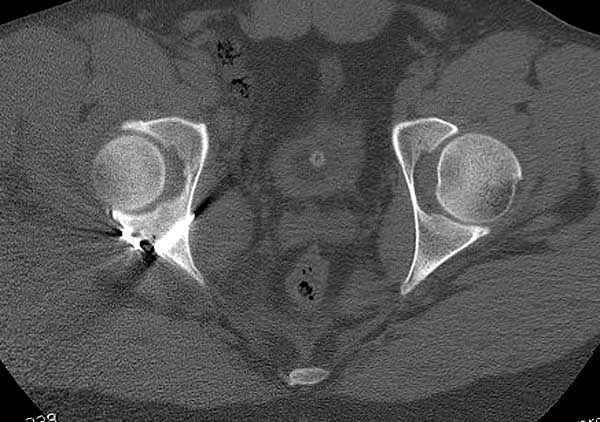

Выставлена на обсуждение (только одна проекция) рентгенограмма больного 25 лет, поступившего в приемное отделение, молодой дежурный врач сомневается в тактике лечения и спрашивает совета.

С его слов, больной стабилен,травму получил в результате автоаварии.Подскажите, что делать?Джолдас Кульджанов

Кроме вывиха виден перелом задней стенки, насчет задней колонны не уверен (видна линия перелома дистальнее ацет. крыши - подвздошная проекция или СТ помогли бы прояснить ситуацию). Поэтому с такой ситуации только закрытое вправление без рефиксации фрагмента задней стенки может привести к рецидиву вывиха (с чем имел неприятность столкнуться не так давно).

На первый взгляд, бедро надо вправить, наложить вытяжение, и дообследовать - Judet views, CT вертлужной впадины, чтобы оценить дефект задней стенки. Вероятно, придется делать остеосинтез заднего края.

5:24 Рентгенограмма таза, вызывают врача ортопеда (снимок N1), его диагноз: закрытый переломо-вывих правого тазабедренного сустава, получает добро на закрытую репозицию в приемном отделении

5:38 Дважды неудачная попытка закрытой репозиции в приемном отделении

N 2

6:20 ответстенный врач принимает решение о репозиции в условиях операционной, предупреждаются родственники и больной, что при неудачной закрытой репозиции, о возможности открытой репозиции и фиксации задней стенки вертлужной впадины.

7:30 начало операции, больной на спине, попытка репозиции после анестезии N3, укладка больного на боку, доступ Kocher- Langenbeck, состояние седалищнего нерва около 2.5см кровоподтек, через joistick головка бедра приподнята, освобовождение сустава, фрагмент заднего края более 3х4 см репонирован на свое место. После промывания

сустава, репозиция вывиха (N4), фиксация фрагмента 2.7(4) мм шурупами и допольнительно реконструктивной пластиной на 8 дырок, фиксация 3.5мм шурупами проксимально и дистально.

Интраоперционные N5 косая запирательная и N6 подвздошный снимок

11:50 больной в послеоперационной, рентгенограмма N7, компьютерная томограмма в тот же день N8-10